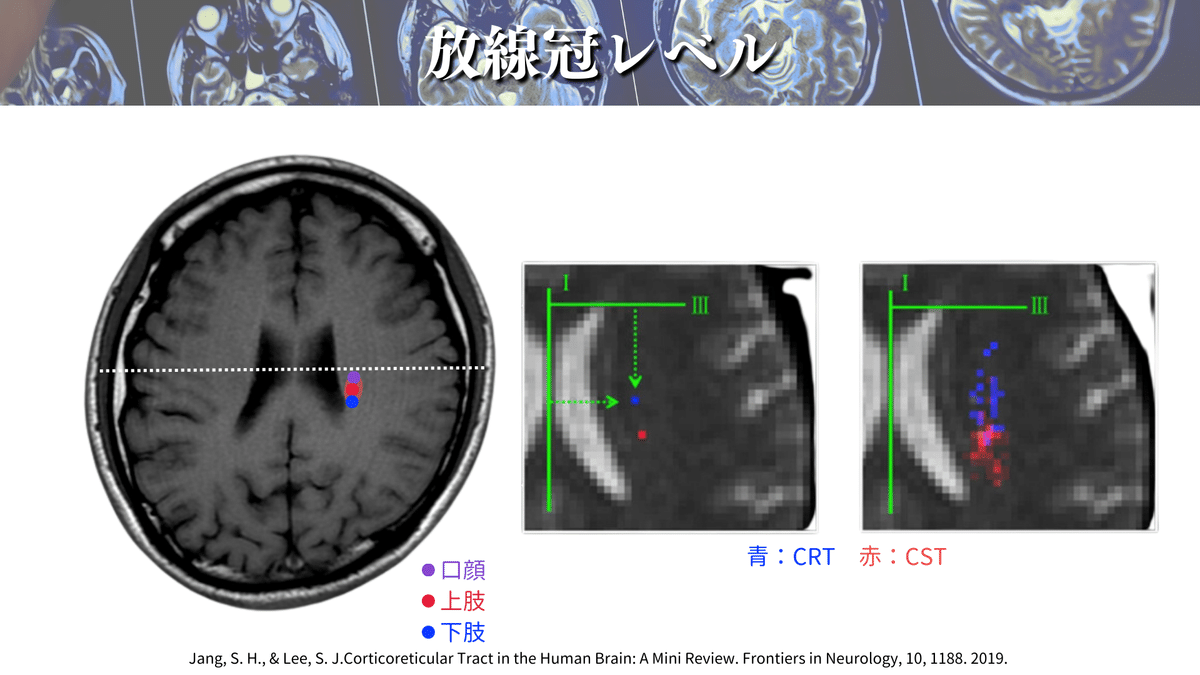

放線冠レベル

このレベルはよく養成校でも解説されるのではないでしょうか🤔?

まずは大まかにCSTに走行を見ていきましょう👀

上図のような場所をCSTは走行していきます🏃♀️

ポイントとしては、側脳室(体部)の真ん中に線を引いて、線よりも下側をCSTが走行するイメージです☝️

さらに解像度を上げると、、、🔍

こんな感じになります😳

やっぱり真ん中の線よりも下側にありそうですよね🤔

放線冠レベルの解説をしている論文は他にも多くあるので、オススメを紹介していきます✨

側脳室の前角や後角、側脳室の壁や島の縁などの距離から、口顔や上下肢のCSTの位置を計算する方法があります☝️

これによると、最も前外側に位置するのが口顔の線維であり、最も後内方に位置するのが下肢の線維ということが一目でわかりますね😳

これらのことから、大体この辺りを通るのかなということがわかったのではないでしょうか?🕵️(上図)